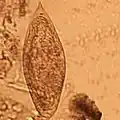

| Cercaria-larve van Schistosoma | |||||||||||

In de slak ondergaan de larven een aantal ontwikkelingsstadia. De miracidia verliezen hun trilharen en veranderen in een moeder-sporocyst: een soort zak waarin de larve zich ongeslachtelijk vermeerdert. Iedere moeder-sporocyst produceert meerdere dochter-sporocysten, die op hun beurt weer talloze cercaria (larven) voortbrengen. Ieder miracidium brengt zo vele honderdduizenden cercaria voort. Ook van de cercaria zijn er mannelijke en vrouwelijke exemplaren.

De cercaria verlaten hun tussengastheer en zwemmen naar hun tweede gastheer. Mensen kunnen besmet raken door te baden, waden, zwemmen, drinken en wassen. De larven dringen de (gave) huid binnen en ontwikkelen zich daar tot een schistosomulum, een nieuw larvestadium. De schistosomula komen in het bloedvatenstelsel terecht, waarin ze uitgroeien tot volwassen mannelijke en vrouwelijke wormen. De exacte leefwijze verschilt per soort.